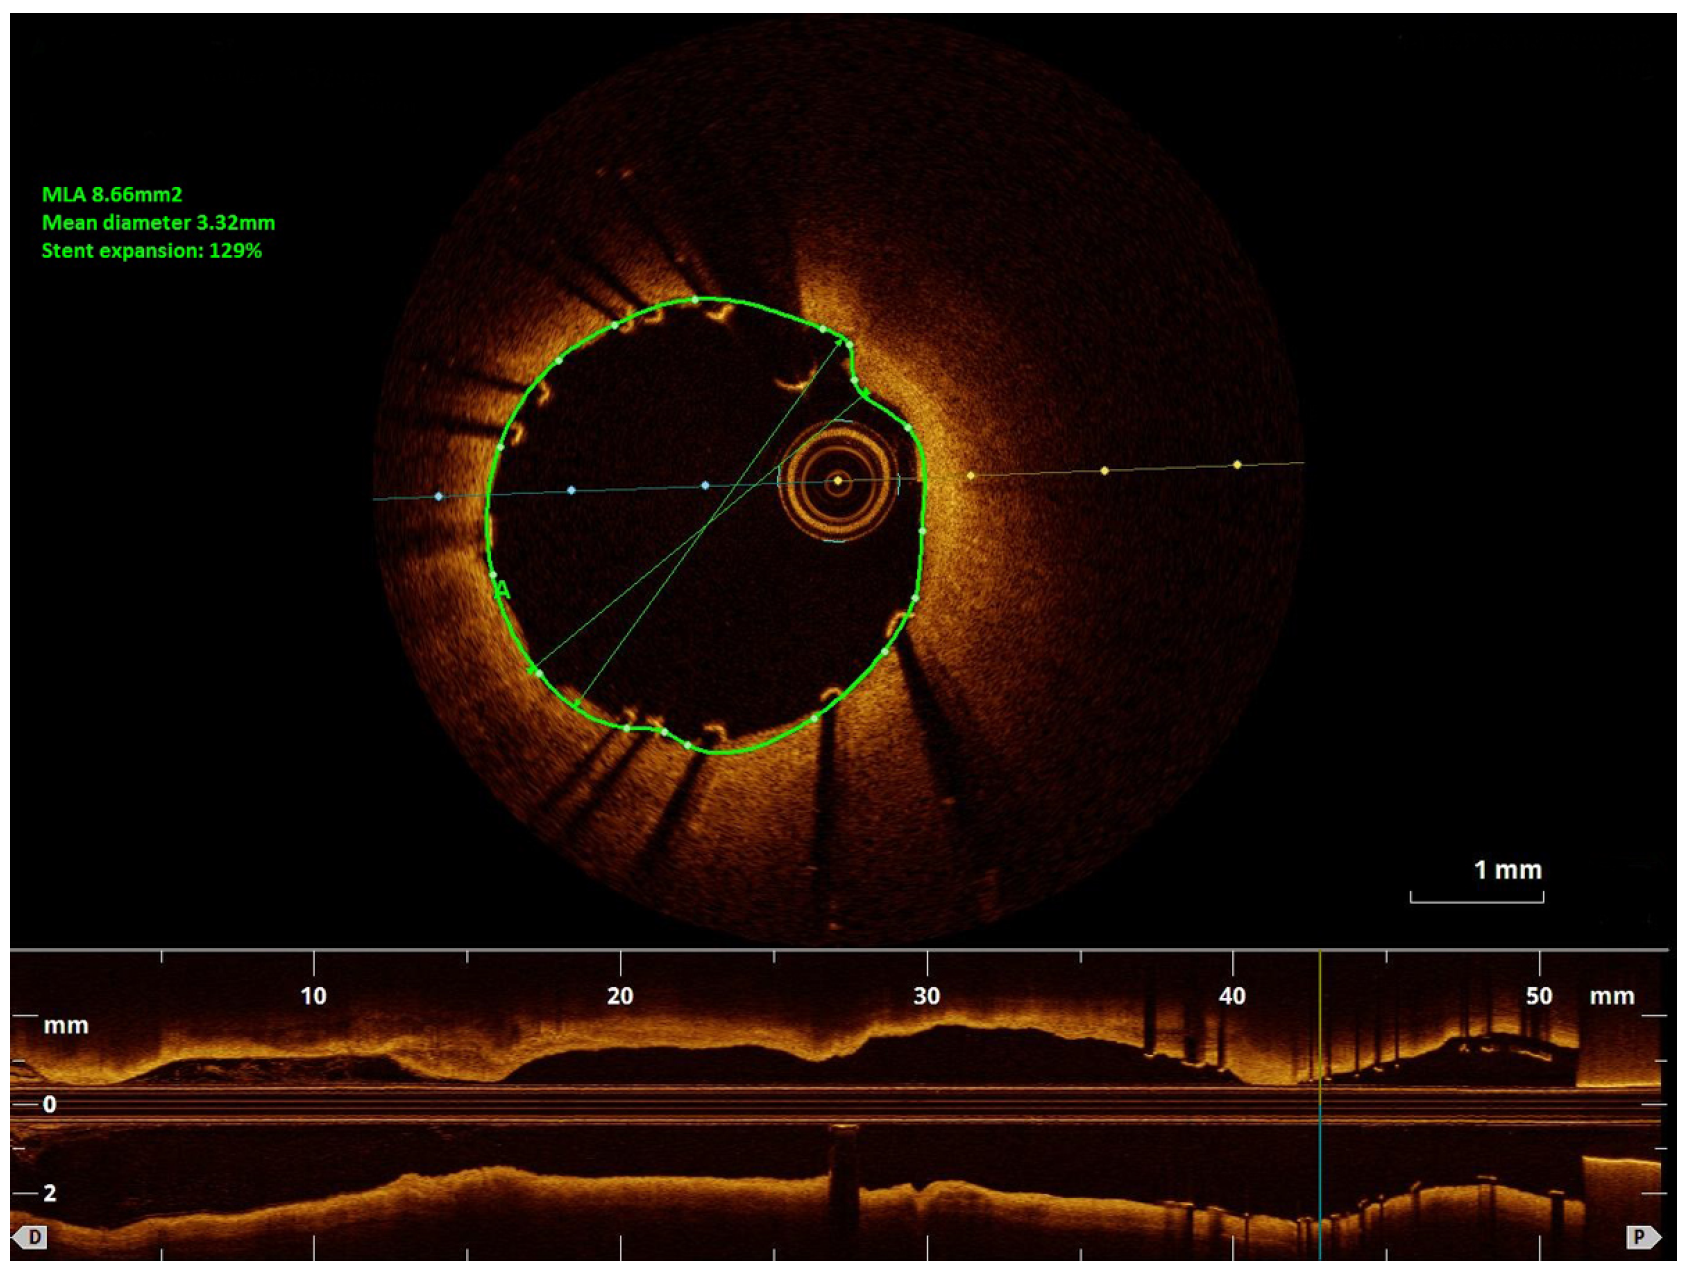

Impressive Late Stent Recoil of a Drug-Eluting Resorbable Magnesium Coronary Stent

Case description